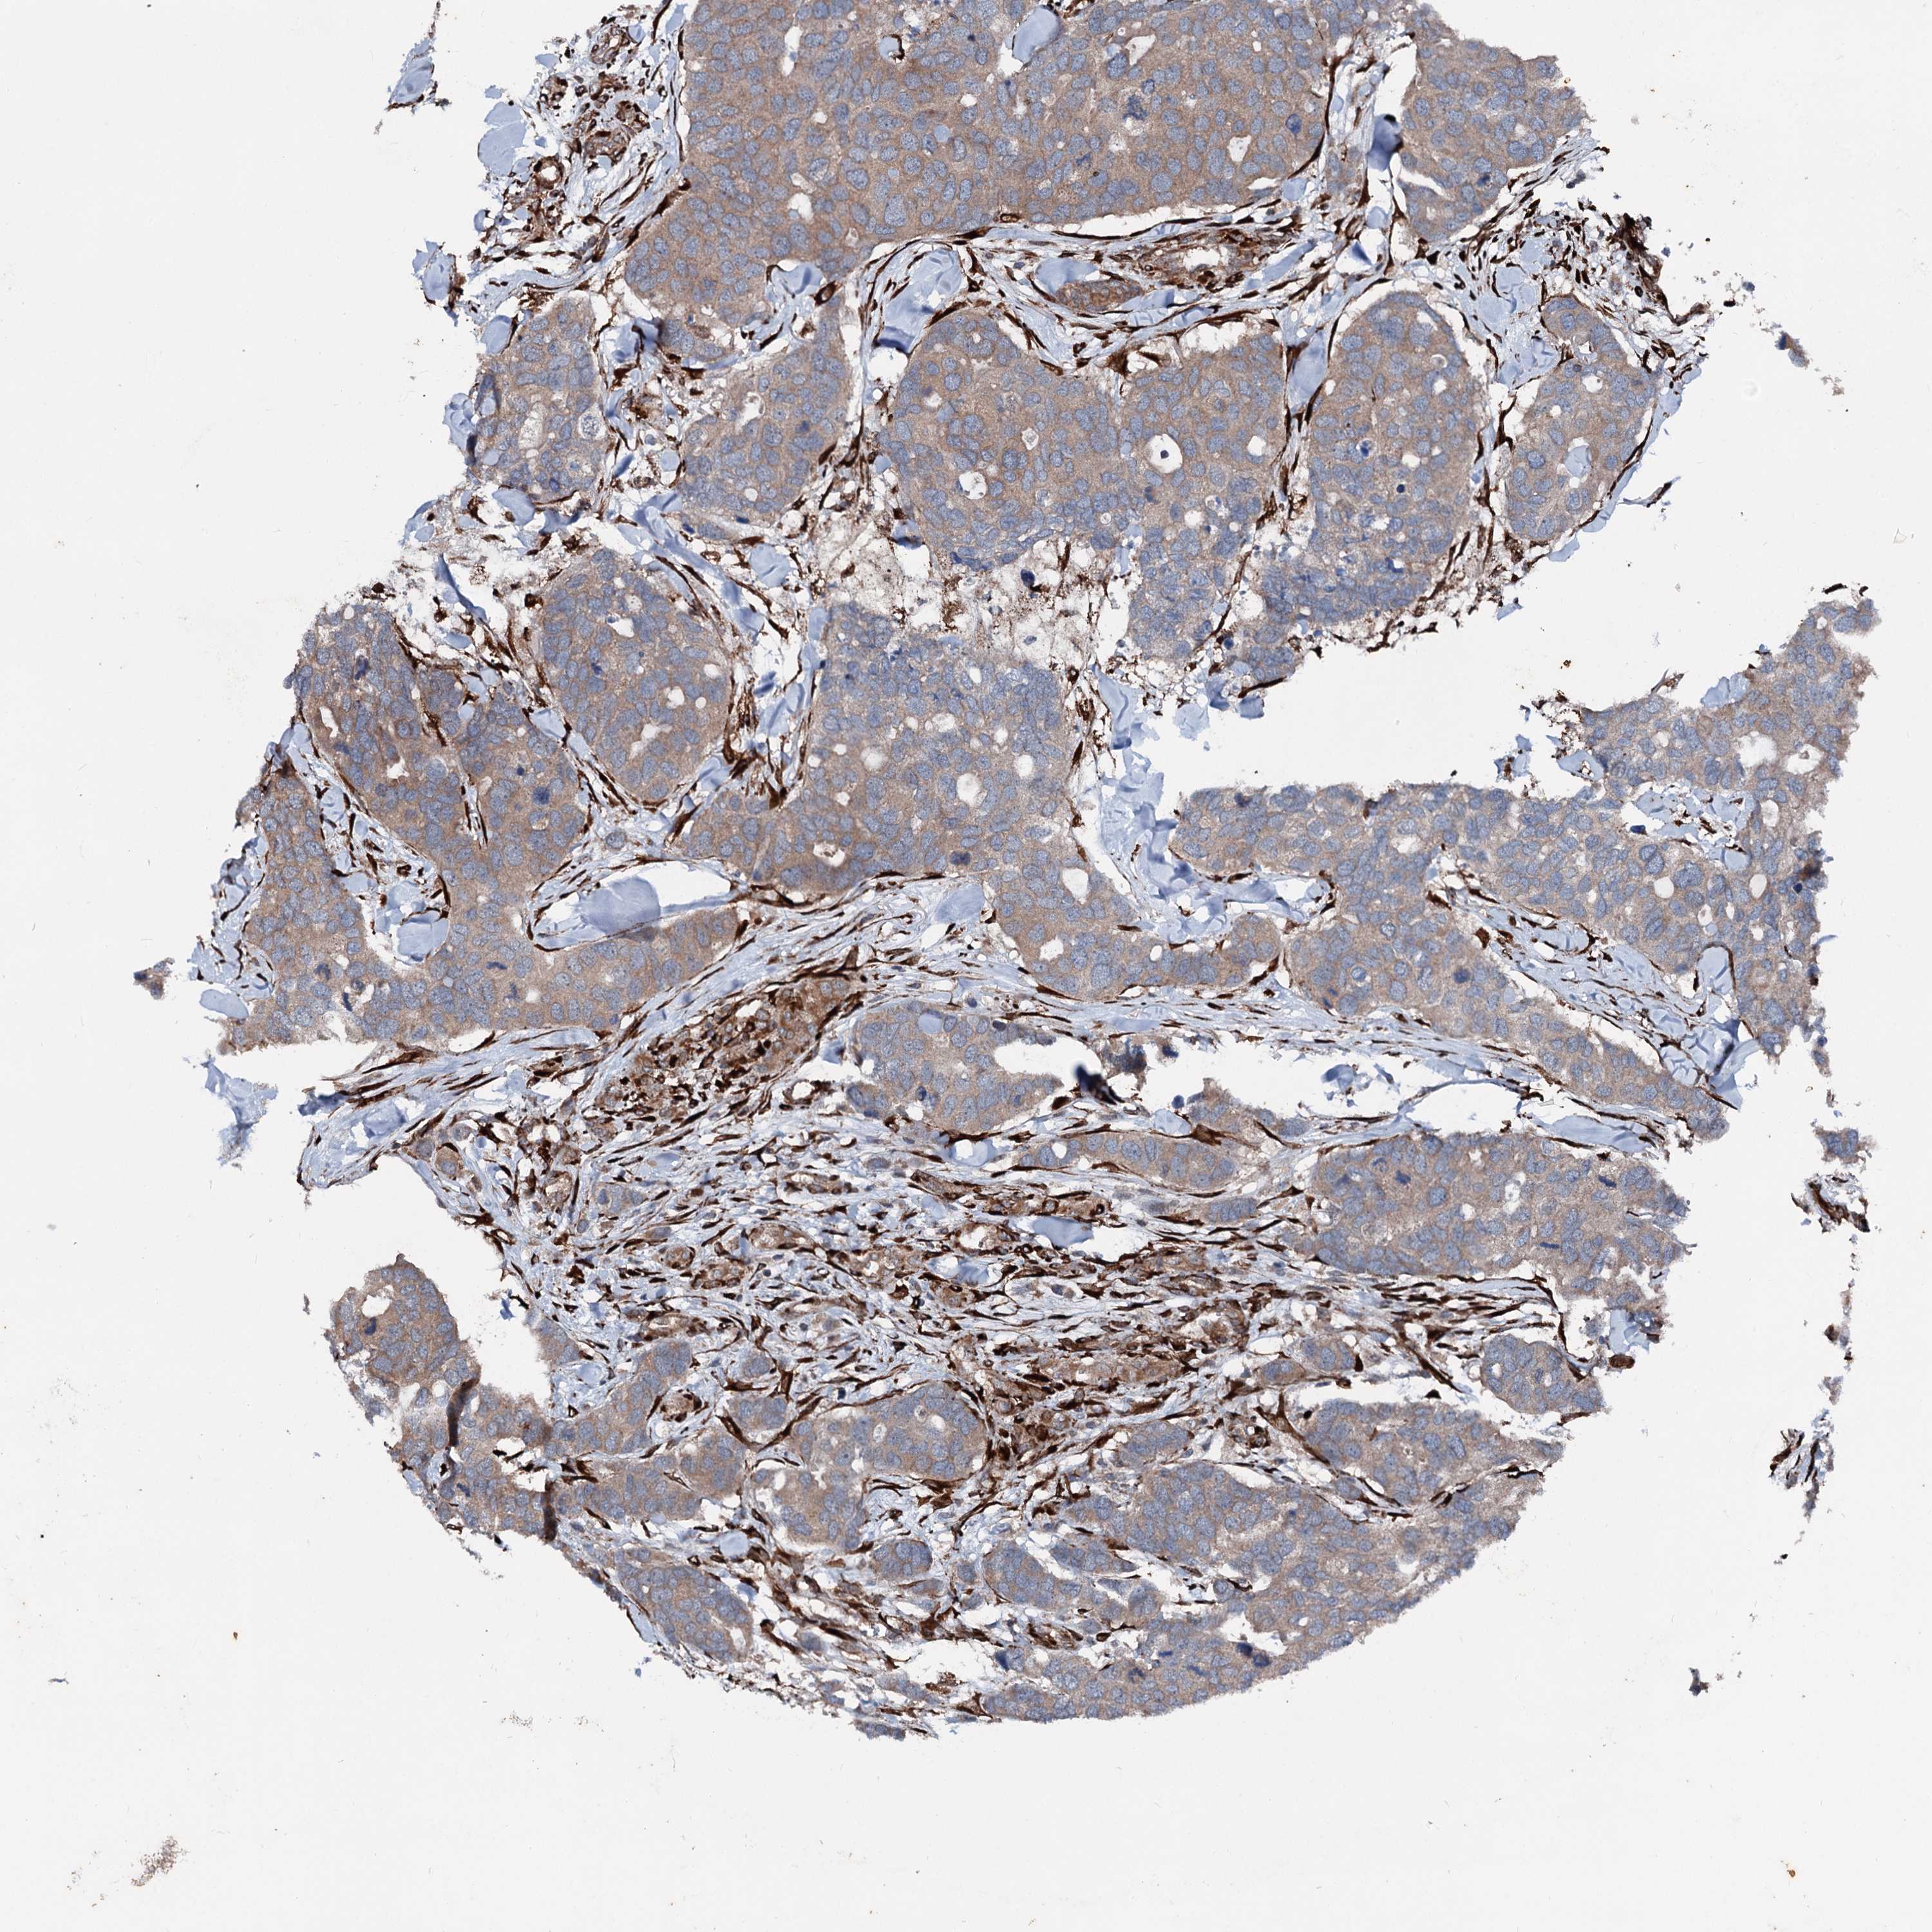

CANCER BREAST CANCER Show tissue menu

BRCA TCGA BRCA VALIDATION PROTEIN EXPRESSION